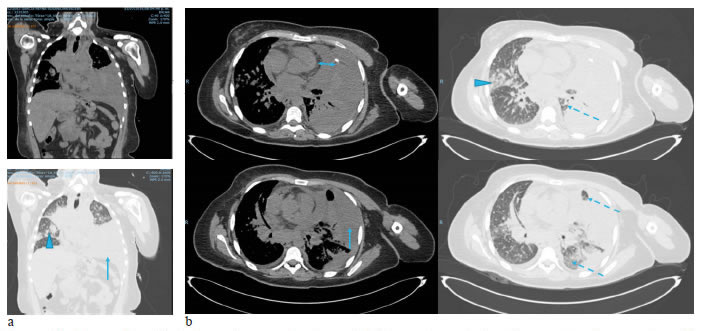

Caso clínico 2. Derrame pericárdico maligno

Se trata de una mujer de 67 años con adenocarcinoma de pulmón T3N2M1a, en etapa clínica IV y 2 en la escala ECOG.

Después de la quimioterapia, en la tomografía por emisión de positrones (PET-CT) se observaron los implantes pleurales, con engrosamiento pleural y pericárdico, y derrame pericárdico. Hubo progresión según los criterios de reacción por PET-CT (Positron Emission Tomography Response Criteria, PERCIST). No se observaron signos de taponamiento cardiaco (figura 6).

Se practicó una ventana pericárdica subxifoidea con instalación de un catéter subcutáneo (tunnelized) pericárdico (figura 7).

El estudio citológico del líquido pericárdico y del bloque celular mostró características serohemáticas; fue positivo para neoplasia maligna: carcinoma (figura 8). La histopatología del tejido obtenido de la ventana pericárdica fue negativa para neoplasia maligna.

Seis semanas después, la paciente tuvo que ser sometida a toracoscopia para evacuar el derrame pleural izquierdo; se tomaron biopsias pleural y pulmonar para evaluar el perfil molecular en las muestras de tejido.